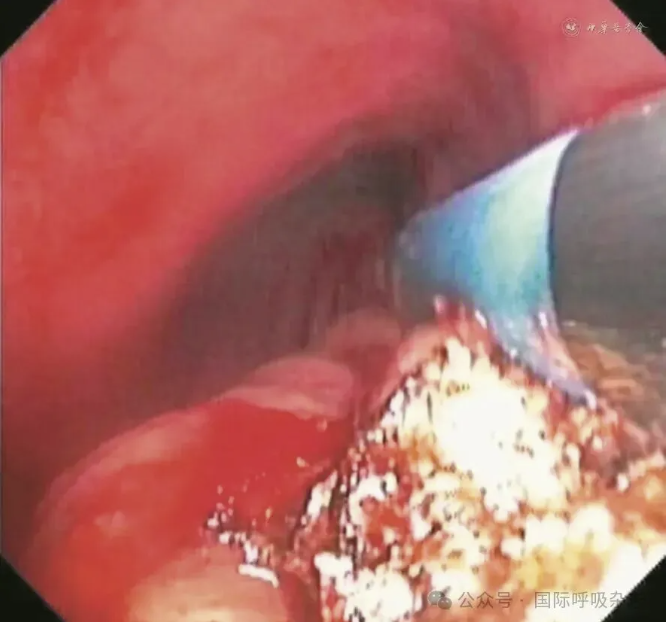

患者男,61岁,因“食管癌术后3年,咳嗽、气喘半年”于2025年3月14日入院。患者于2022年确诊食管鳞癌,曾接受新辅助免疫联合化疗、食管癌根治术、术后辅助免疫治疗、局部放疗及多线化疗等规范治疗。2024年12月经胃镜检查确诊为“气管食管瘘”,遂行空肠营养管置入术(图1)。后因咳嗽、气喘症状持续,辗转多家医院治疗效果不佳就诊于西安市胸科医院。入院查体:端坐呼吸,声音嘶哑,双肺可闻及湿性啰音及喘鸣音。实验室检查示炎症指标升高:白细胞计数8.82×109/L,中性粒细胞比例88.8%,C反应蛋白165.88 mg/L。血气分析pH值7.435,PaCO2为45.2 mmHg(1 mmHg=0.133 kPa),PaO2为55 mmHg,氧合指数200 mmHg,提示Ⅰ型呼吸衰竭。胸部CT提示气管食管瘘,伴双下肺感染及实变(图2)。支气管镜下见气管中下段膜部菜花样新生物,新生物下方可见瘘口(图3)。

图3:61岁男性气管食管瘘患者支气管镜检查(2025年3月15日)示气管中下段膜部可见菜花样新生物,于新生物下方可见气泡冒出,考虑瘘口形成